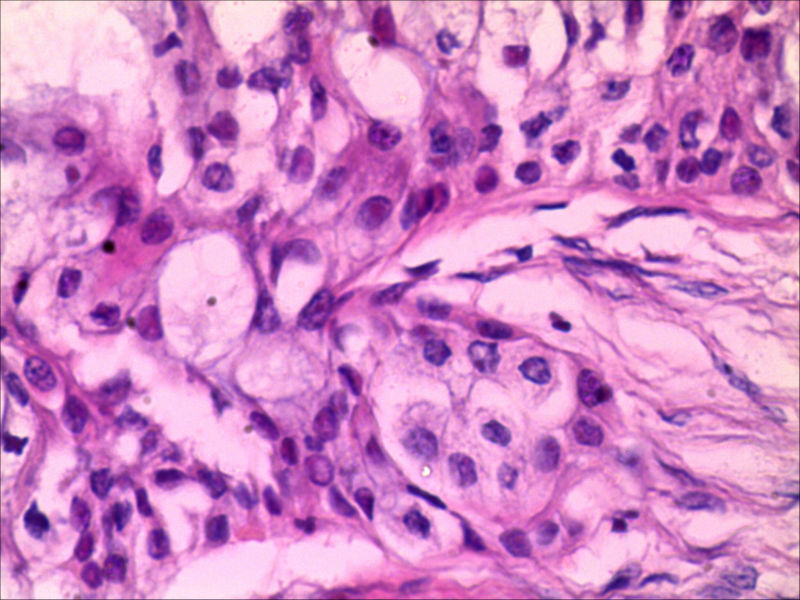

右下颌肿物女26岁 大家帮帮看看

典型的黏液表皮样癌,低度恶性。

本例可以看到典型的产粘液细胞、鳞状细胞、中间细胞和透明细胞,因为产粘液细胞多,甚至形成粘液湖,加之包块似有包膜,分界清楚,应该考虑粘液表皮样癌(低度恶性)。